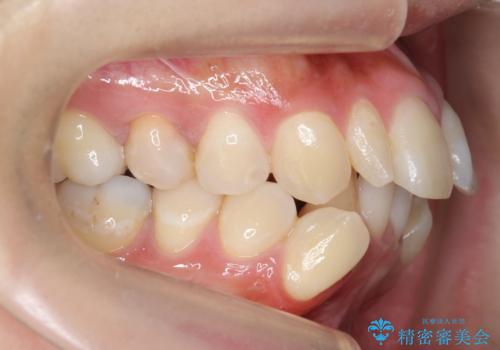

矯正治療で歯並びを治した後、乳歯を抜いたところにブリッジを入れています。

左上の奥歯はすれ違っていたためそのかみ合わせも整えています。

歯を抜いて治療を行ったため、Eラインが整った形で治療ができました。口が断然閉じやすくなっています。